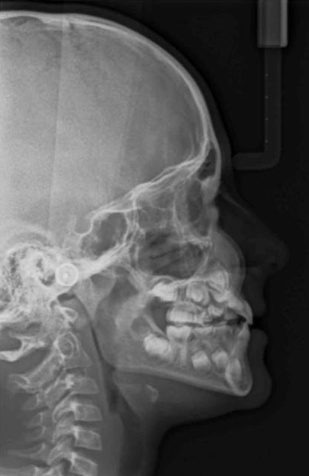

Radiologie

Le cabinet est équipé d’un appareil radiologique KODAK 8000 ceph permettant la réalisation de panoramique et de téléradiographie nécessaires à la réalisation des bilans orthodontiques et au suivi thérapeutique. Ces radiographies numérisées sont de qualité optimale avec des doses minimales d'irradiation.